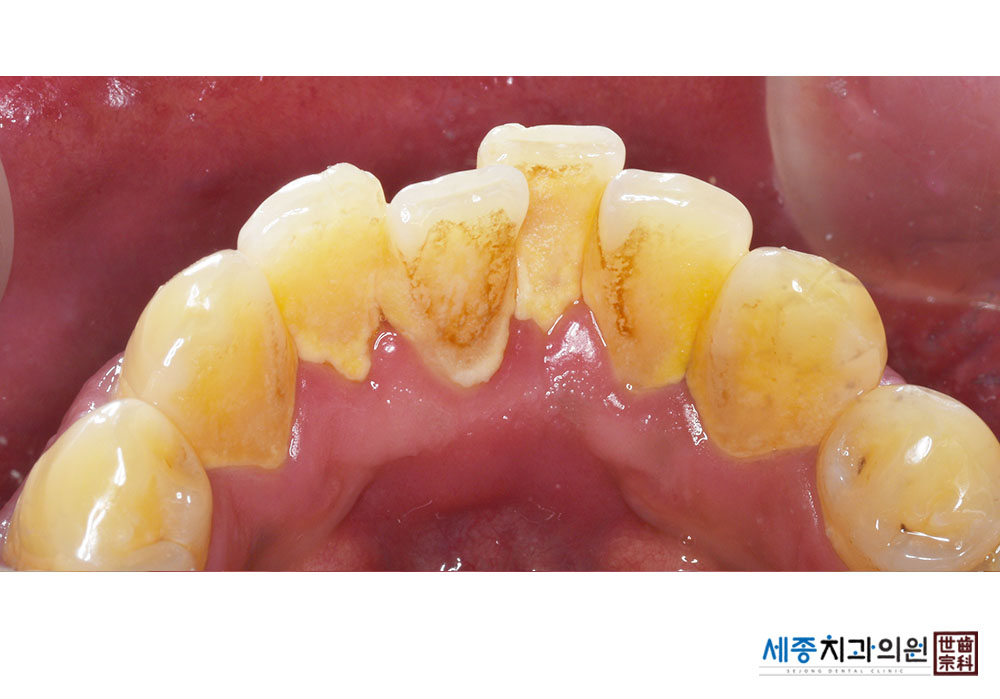

[스케일링] 치주질환 예방 스케일링

치료전 : 2022-12-28

가글마취&저주파 스켈러를 사용한 스케일링